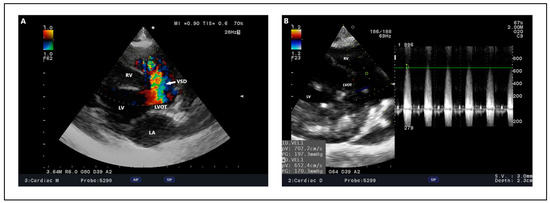

Veterinary cardiology has become a permanent fixture, both in the way of services provided by general practitioners, and also in specialized centers, which are being established in growing numbers around the world. Acquired heart disease, which develops and progresses with age, accounts for the vast majority of cardiac cases. They are also the subject of greatest interest to researchers, due to the prevalence and difficulties encountered during their treatment. Among them, the most common are myxomatous mitral valve disease in small-breed dogs, dilated cardiomyopathy in large-breed dogs and hypertrophic cardiomyopathy in cats. In contrast, congenital heart defects, which are significantly less common, can pose considerable diagnostic challenges and be cumbersome in terms of selecting the optimal treatment protocol. Due to the rapidly developing branch of interventional cardiology, including minimally invasive procedures, a growing number of defects, such as patent ductus arteriosus, pulmonic stenosis, atrial septal defects or ventricular septal defects, can be successfully addressed by surgical methods. In many cases, such treatment results in a complete recovery, which positively affects the rest of the animal's life. With the use of advanced diagnostics, such as 3D and 4D transesophageal echocardiography, cardiac magnetic resonance imaging (MRI), and cardiac computed tomography (CT), the characteristics of acquired and congenital defects and their complexities can be assessed very accurately, favoring the selection of optimal treatment methods, as well as allowing the determination of possible strategies for surgery. Thanks to this comprehensive approach, veterinary cardiology services in many countries around the world have achieved incredibly high standards of care.